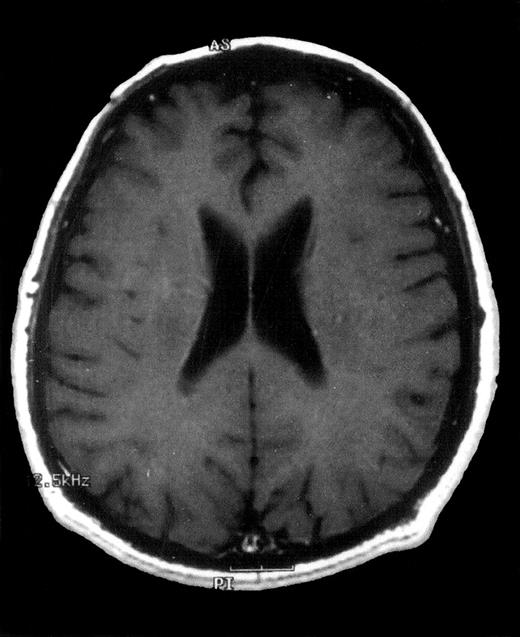

Axial contrast-enhanced T1-weighted MRI image of the brain 12 months after diagnosis.

Complete disappearance of intracerebral lesions after treatment with oral itraconazole.

A 52-year-old man was admitted to our department with asymptomatic severe thrombocytopenia (18 × 109/L), found on a routine full blood count (FBC). Clinical examination was unremarkable. Routine blood chemical values were normal, and tumor markers were negative. Serological tests for hepatitis B and C viruses, cytomegalovirus, Epstein-Barr virus, herpes simplex virus, herpes zoster virus, and human immunodeficiency virus (HIV) were negative. The patient had no clinical or laboratory evidence of autoimmune or immunodeficiency syndromes. Findings on chest radiograph and computed tomography (CT) scans of the chest, abdomen, and pelvis were normal. A bone marrow smear revealed normal numbers of megakaryocytes in an otherwise normal bone marrow, while antiplatelet IgG and IgM antibodies were positive. Treatment was initiated with 1 mg/kg oral MP daily, and 3 days later the patient was discharged after a prompt recovery of the platelet (PTL) count (70 × 109/L). The patient was followed up at the outpatient clinic, and tapering of MP was initiated after 4 weeks of treatment, while corticosteroid-induced type 2 diabetes mellitus developed. Eight weeks later, while on 24 mg MP daily, the patient was readmitted, afebrile and with a 3-day history of fatigue and palpitation. The FBC revealed a normal hemoglobin level and white blood cell and platelet counts. A radiograph of the chest showed patchy, nodular consolidations in both lungs. MP was tapered to 16 mg every other day (and discontinued on the 14th day of hospital stay), while cotrimoxazole, ceftriaxone, clarythromycin, and fluconazole were administered. Repeat virology (including HIV) and immunological laboratory tests again excluded any underlying autoimmune or immunodeficiency syndromes. Culture specimens of blood, sputum, and urine were negative for microorganisms. A bone marrow smear was unremarkable. Microscopical examination of a stained specimen of sputum showed no acid-fast bacilli. A urine test for legionella antigen was negative. On the fifth day of hospital stay, the patient became febrile (39°C) and developed a bloodstained productive cough. A chest radiograph revealed an increase in the bilateral nodular and patchy consolidations, while a CT scan of the chest on the eighth day of hospital stay showed bilateral multifocal nodules with cavitation. Amphotericin 1.5 mg/kg IV and itraconazole 400 mg daily were initiated. On the 10th day of hospital stay, a bronchoscopy was performed and aspergillus fumigatus was isolated from bronchoalveolar lavage fluid samples. The patient showed no clinical or radiological improvement over the following days and was switched to liposomal amphotericin 5 mg/kg, while itraconazole was increased to 800 mg daily. The patient showed a slow but stable improvement and, on the 27th day of hospital stay, became afebrile. On the 30th day of hospital stay, the patient developed a brief Jacksonian-type seizure. Magnetic resonance imaging (MRI) of the brain disclosed multiple (19 in total) ring-shaped brain abscesses. T1- and T2-weighted images showed low-intensity lesions containing high-intensity areas and high-intensity lesions, respectively (Figure 1). Cerebrospinal fluid (CSF) revealed a glucose level of 64 mg/dl (serum glucose 160 mg/dl), 2 cells/mm3, 15 RBC/mm3, and 55-mg/dl protein. Microscopic examination (gram staining, acid-fast bacilli, fungi) and CSF cultures were sterile. Serum and CSF enzyme-linked immunosorbent assay antigen test for IgA, IgM, and IgG toxoplasma gondii antibodies and CSF latex agglutination tests for aspergillus and cryptococcus neoformans antigens were negative. The good condition of the patient and the small size of the intracerebral lesions (the largest, 19 mm in diameter) discouraged neurosurgeons from performing a stereotactic biopsy. Although central nervous system (CNS) toxoplasmosis was most unlikely, a 2-week trial of sulfadiazine and pyramethamine was initiated, and follow-up CT scans of the brain failed to show improvement in the lesions, ruling out CNS toxoplasmosis. We persisted with antifungal treatment, and the pulmonary lesions gradually improved while the brain lesions remained unchanged in number and size. On the 60th day of hospital stay, the patient was discharged with itraconazole 400 mg daily, in good condition and with marked improvement of pulmonary lesions but stable cerebral lesions. Over the next months, follow-up CT scans showed a slow improvement of the intracerebral lesions, while a 12-month follow-up MRI scan disclosed complete resolution of these lesions (Figure2). The presenting features and the clinical course yielded an apparent diagnosis of cerebral aspergillosis.